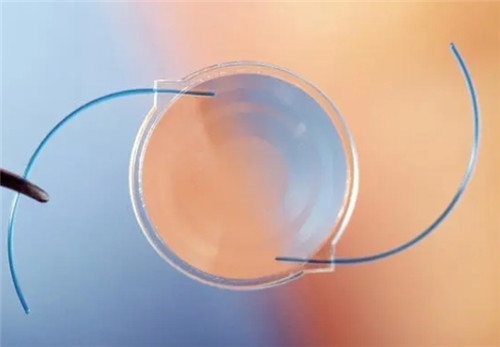

三焦点晶体:相比传统单焦点,可同时优化远、中、近视力,术后不用戴老花镜。

设备靠前,术前检查超全(OCT、角膜地形图等)。

严格术前评估:确保患者符合手术条件,降低术后眩光等风险。